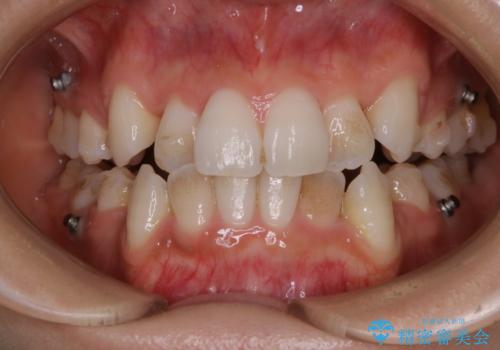

表のワイヤー装置で矯正中にPMTCで綺麗にお掃除

担当医 歯科衛生士